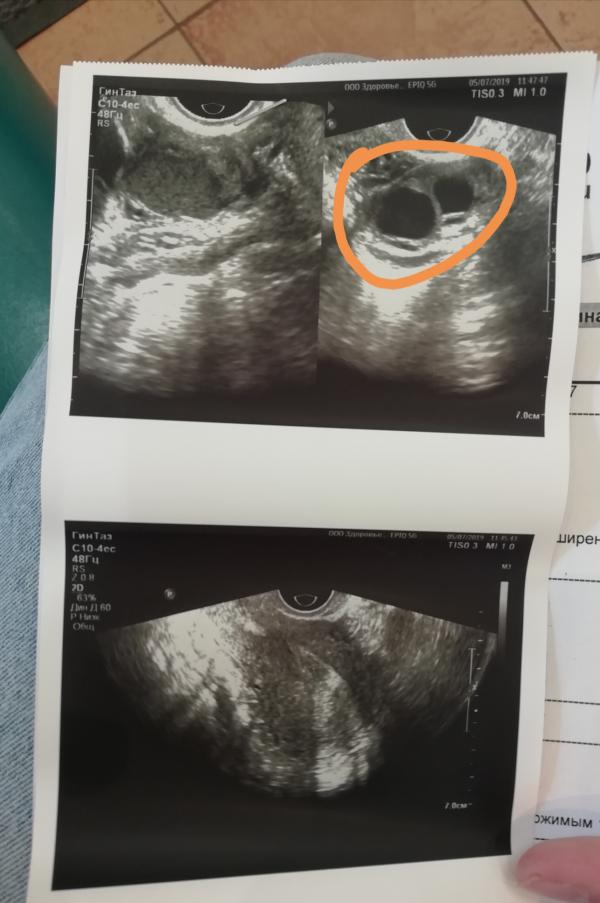

Девочки, всем добрый вечер. У меня два месяца назад обнаружили эндометриоидную кисту правого яичника 2-3см, сказали ещё сделать повторно узи через три месяца. Я уже на днях ещё раз сделала узи, сказали, что рядышком ещё одна маленькая образовалась. Записалась на консультацию к гинекологу. У кого была похожая ситуация, диагноз, как лечили? Начиталась, что гормональные совсем не помогают, только лапароскопия. Ещё один вопрос :я не Казанская, где можно сделать эту операцию? Сколько стоит? Буду всем благодарна ♥️